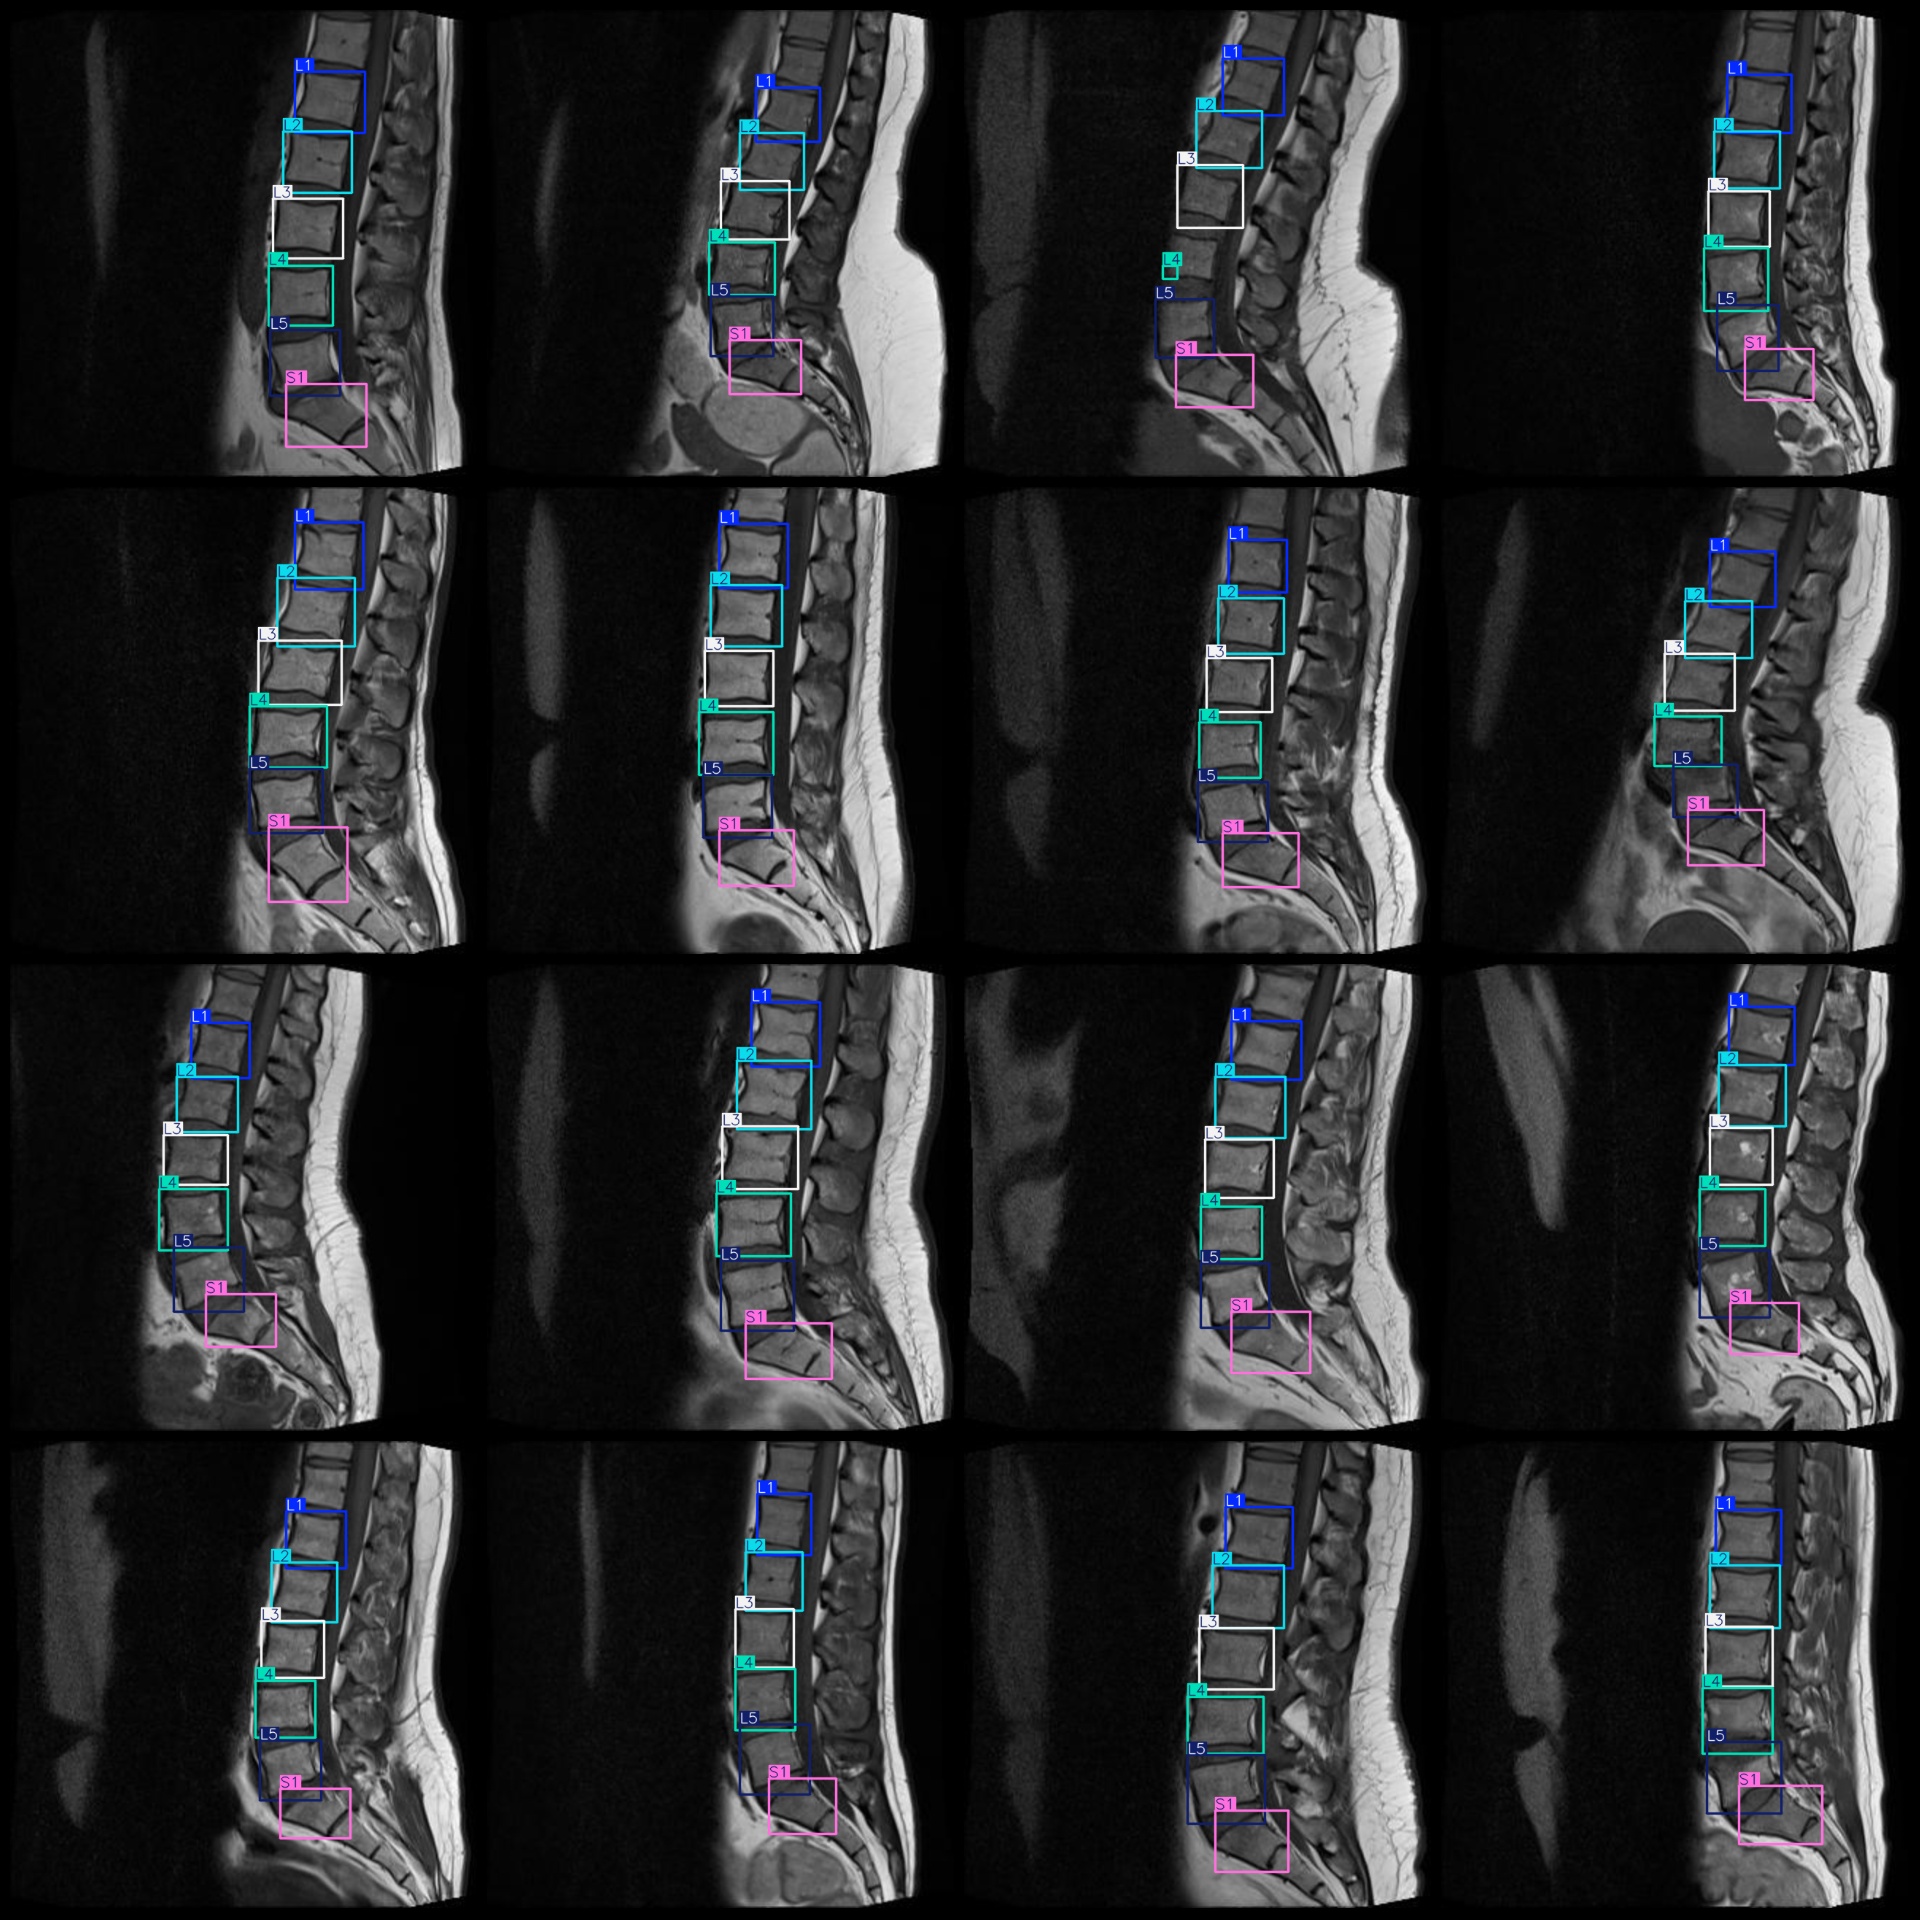

图片预览:

标注例子:

标注类别名称(注意yolo格式类别顺序不和这个对应,而以labels文件夹classes.txt为准):["L1","L2","L3","L4","L5","S1"]

标注类别数:6

标注规则:对类别进行画矩形框